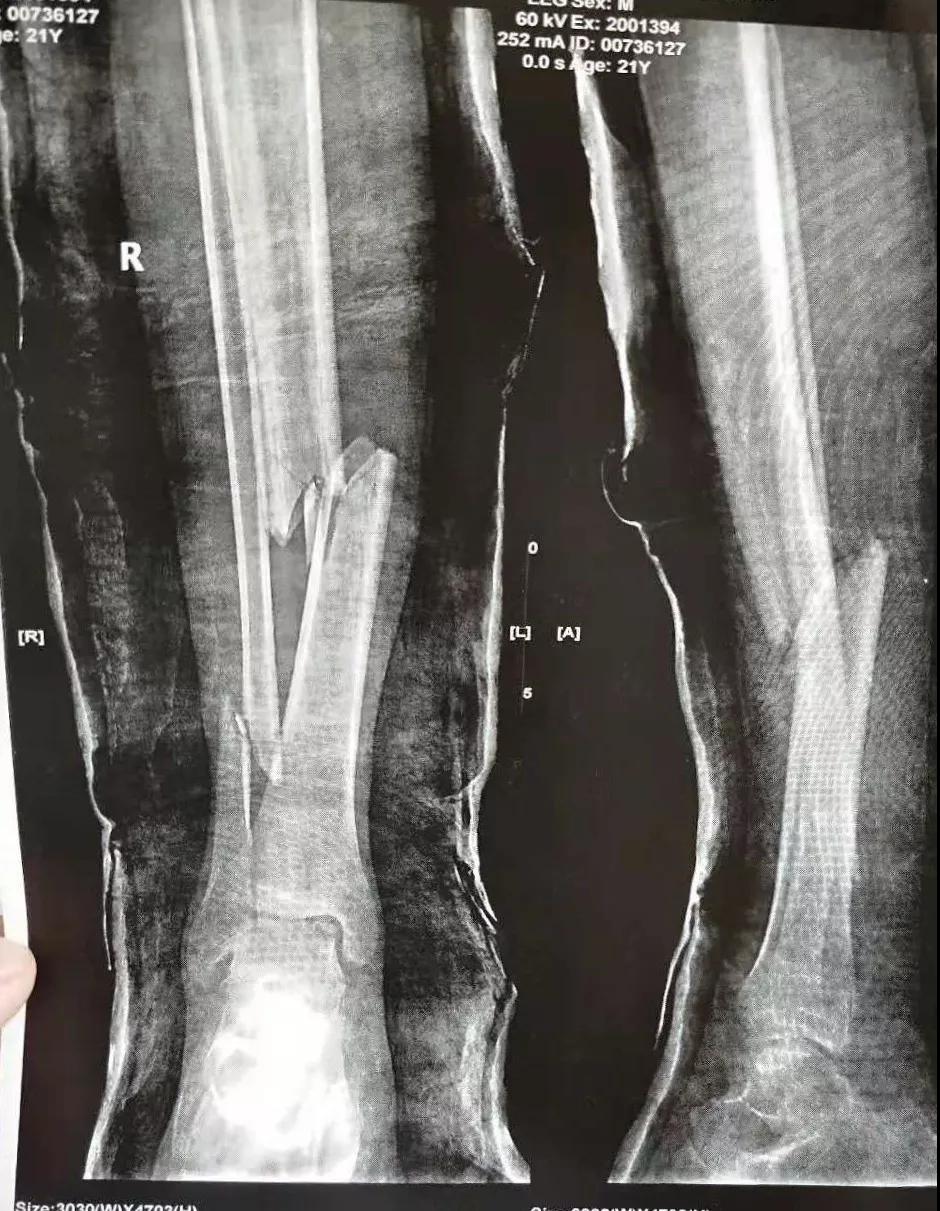

这名21岁的男性患者一个月前因车祸致伤,在当地某三甲21点游戏规则 确诊为右胫腓骨粉碎性骨折,骨折移位明显,建议手术治疗,因既往患严重慢性再生障碍性贫血病史16年,一般状况差,需长期输注血液制品维持三系细胞水平,麻醉及手术风险极高。虽经当地积极内科治疗,患者一般状况仍差,无法耐受手术治疗。患者及家属经多方打听,抱着最后一丝希望来到我院骨二科求治。

骨二科张延平主任接诊后经仔细询问病史,详细阅读近期X线、CT等病历资料,认为患者骨折移位明显,目前骨折无任何愈合迹象,若保守治疗,骨折将无法愈合,后期不能下地活动,严重影响患者生活质量。同时患者合并慢性再障,血常规结果各项指标均极低,围术期发生麻醉意外、大出血、感染等风险极高;而我院作为西安市级最大的三甲综合21点游戏规则 ,综合实力深厚,既往相关疾病治疗经验丰富,多次通过多学科诊治为合并复杂内科疾病患者保驾护航,为患者创造手术时机,提高患者生活质量,遂将患者收住院。住院后,立即成立了由张延平主任、杨寅副主任、山卉护士长、梁晨主治医师、刘邦定主治医师、李鑫护师组成的手术治疗小组。经初步检查,患者血常规结果较当地检验结果更差,三系细胞均极低,其中血小板仅为1(正常值为100-300),血红蛋白55g/L。遂立即请血研所李罡灿主任医师会诊,给予升高白细胞、纠正贫血、升高血小板等治疗,经积极治疗患者血常规各项指标均较入院时改善。张延平主任再次组织由血研所李罡灿主任医师、麻醉科崔晓岗主任、感染科付建军主任、药剂科韩小年副主任药师等参加的术前讨论。讨论后一致认为患者目前各项指标虽然较入院时改善,但因其慢性再障病史长,骨髓造血及储备能力极差,围术期发生大出血、伤口感染甚至全身感染等风险仍极高,术中及术后需准备大量血小板防止大出血,同时需高度警惕手术切口、取骨区术后发生感染。为尽快为患者施行手术,治疗小组积极联系输血科为患者备血,并为患者制定了围术期抗感染方案;在我院输血科存血量严重不足的状态时,输血科张养民主任亲自联系市中心血站为患者准备手术中及术后所需的血小板制品。手术小组为患者制定了周密的手术方案及风险预案,10月31日,在麻醉科王永宏副主任医师、手术室高洁、赵耀护师的配合下,为患者施行了右胫骨粉碎性骨折切开复位、髂骨取骨植骨内固定术,手术历时70分钟,安全返回病房。术后患者渗血多,1周内连续每日平均渗血超过100ml,并出现发烧,最高39℃,复查血常规三系细胞较术前再次明显降低。李罡灿主任医师、付建军主任、韩小年副主任药师多次来科会诊,及时调整患者的治疗方案,输血科再次为患者的救治提供了强有力的支援和保障。在山卉护士长带领的护理团队精心护理下,患者未发生压疮等卧床并发症。目前该患者术后恢复良好,已出院进行下一步康复治疗。